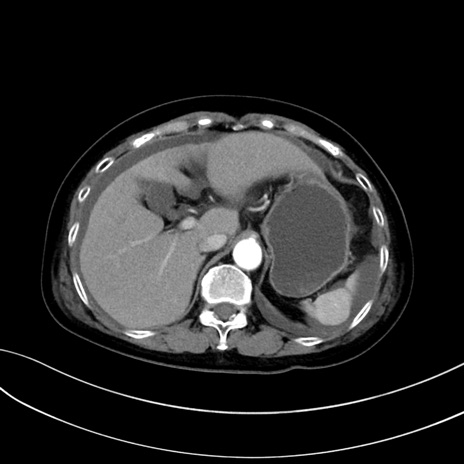

(冠状断像)1日半後